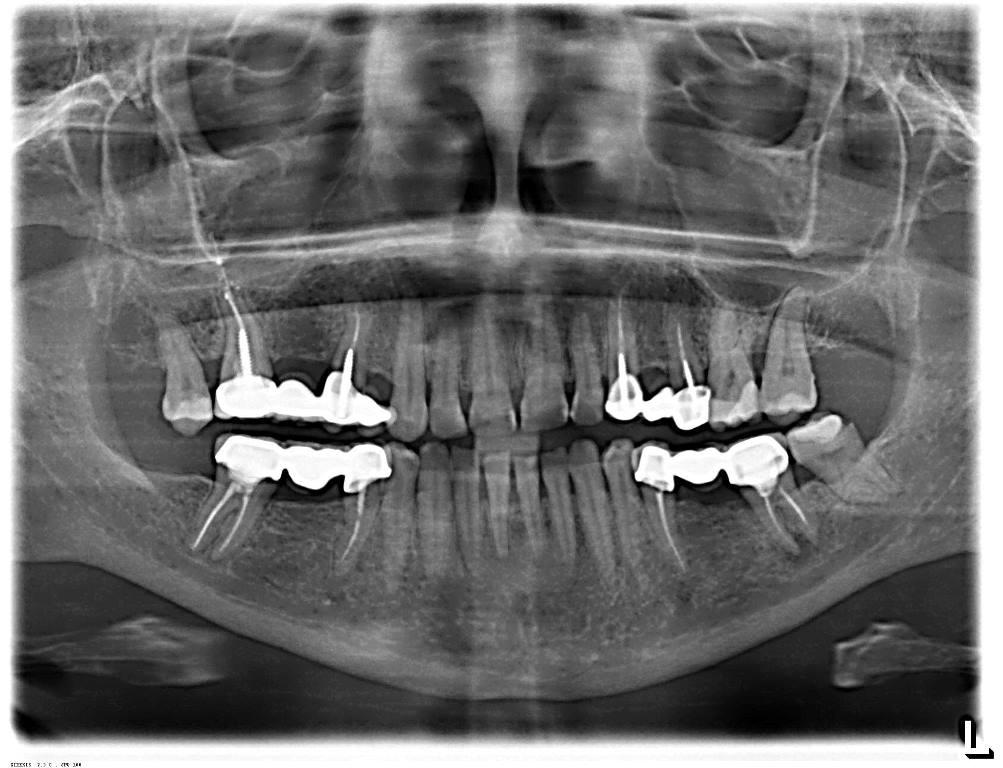

Дентальные снимки и диагностика кариеса